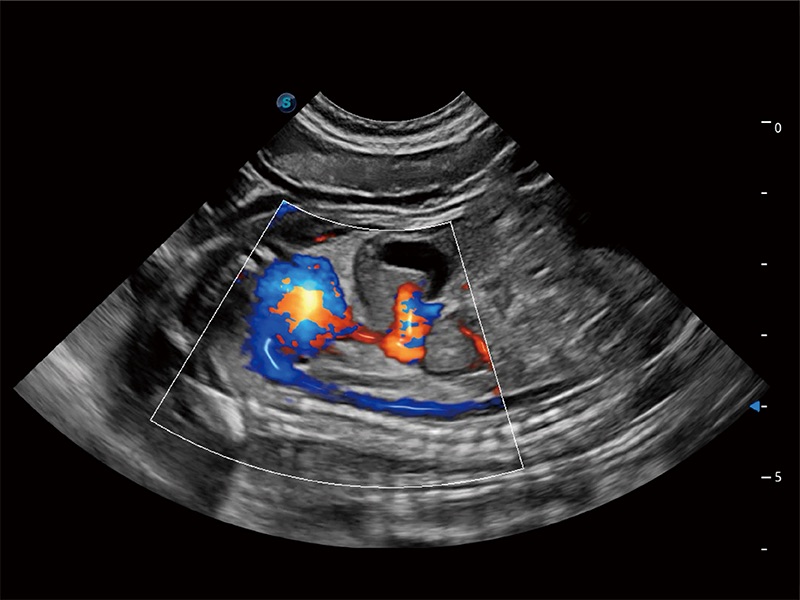

(犬)四腔心MQA

• MQA 心肌定量分析

通过心肌识别技术与二维斑点追踪技术相结合,对心脏的超声图像进行量化分析。计算心肌17个节段的应变、应变率、速度、位移等,并通过牛眼图的形式进行呈现。